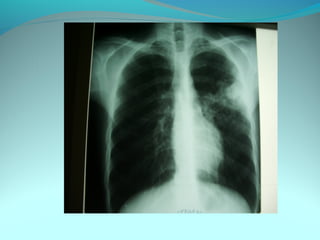

Cliché normal